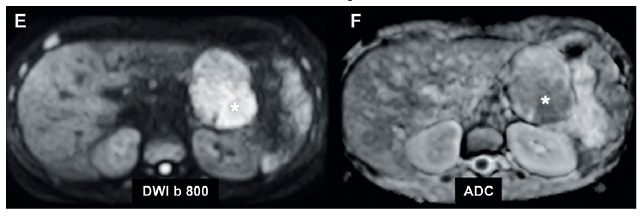

Se realizó una resonancia magnética (RM) de abdomen, que confirmó la presencia de una masa sólido-quística hipovascular, encapsulada, dependiente del aspecto anterior del cuerpo-cola del páncreas (Figuras 1 y 2), cuyos componentes sólidos restringían en la secuencia de difusión (DWI/ADC), presentando algunos tenues focos de alta señal en secuencias ponderadas en T1 que hacían suponer la presencia de residuos de material hemático en su espesor. Esta masa medía 7,9 x 5,4 x 6,6 cm en sus ejes mayores e indentaba ampliamente la vena esplénica, sin obliterarla ni infiltrarla (Figura 1). El resto del parénquima del páncreas mantenía una arquitectura y señal normales, sin dilatación del conducto pancreático principal, adenopatías retroperitoneales ni ascitis.